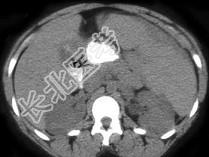

- 单项选择题患者有镰刀形红细胞特征,结合图像, 最可能的诊断为 ( )

A、脾梗死

B、脾脓肿

C、脾出血

D、脾隔离症

E、以上都不是